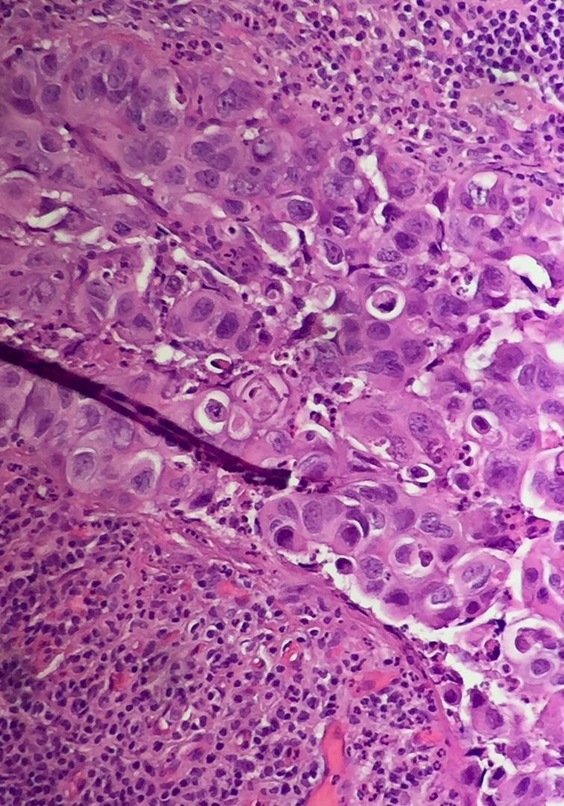

Breast Paget's Disease NUS Pathweb NUS Pathweb Paget's Disease Breast Diagnosis paget's disease and dcis. Your healthcare provider may attempt to treat your condition as eczema. people with paget disease of the breast have often had symptoms for several months before being correctly diagnosed. paget's disease of the breast is a rare cancer of the nipple and areola (the darkened skin around the nipple) closely. tests and. Paget's Disease Breast Diagnosis.